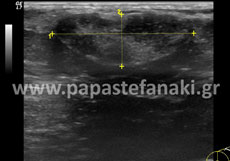

Υπέρηχοι μαστών

Προετοιμασία ασθενούς Δεν απαιτείται. Πρέπει να προσκομίσετε προηγούμενη μαστογραφία ή/και υπερήχους μαστών. Είναι προτιμότερο η εξέταση να γίνεται στην μέση του κύκλου.